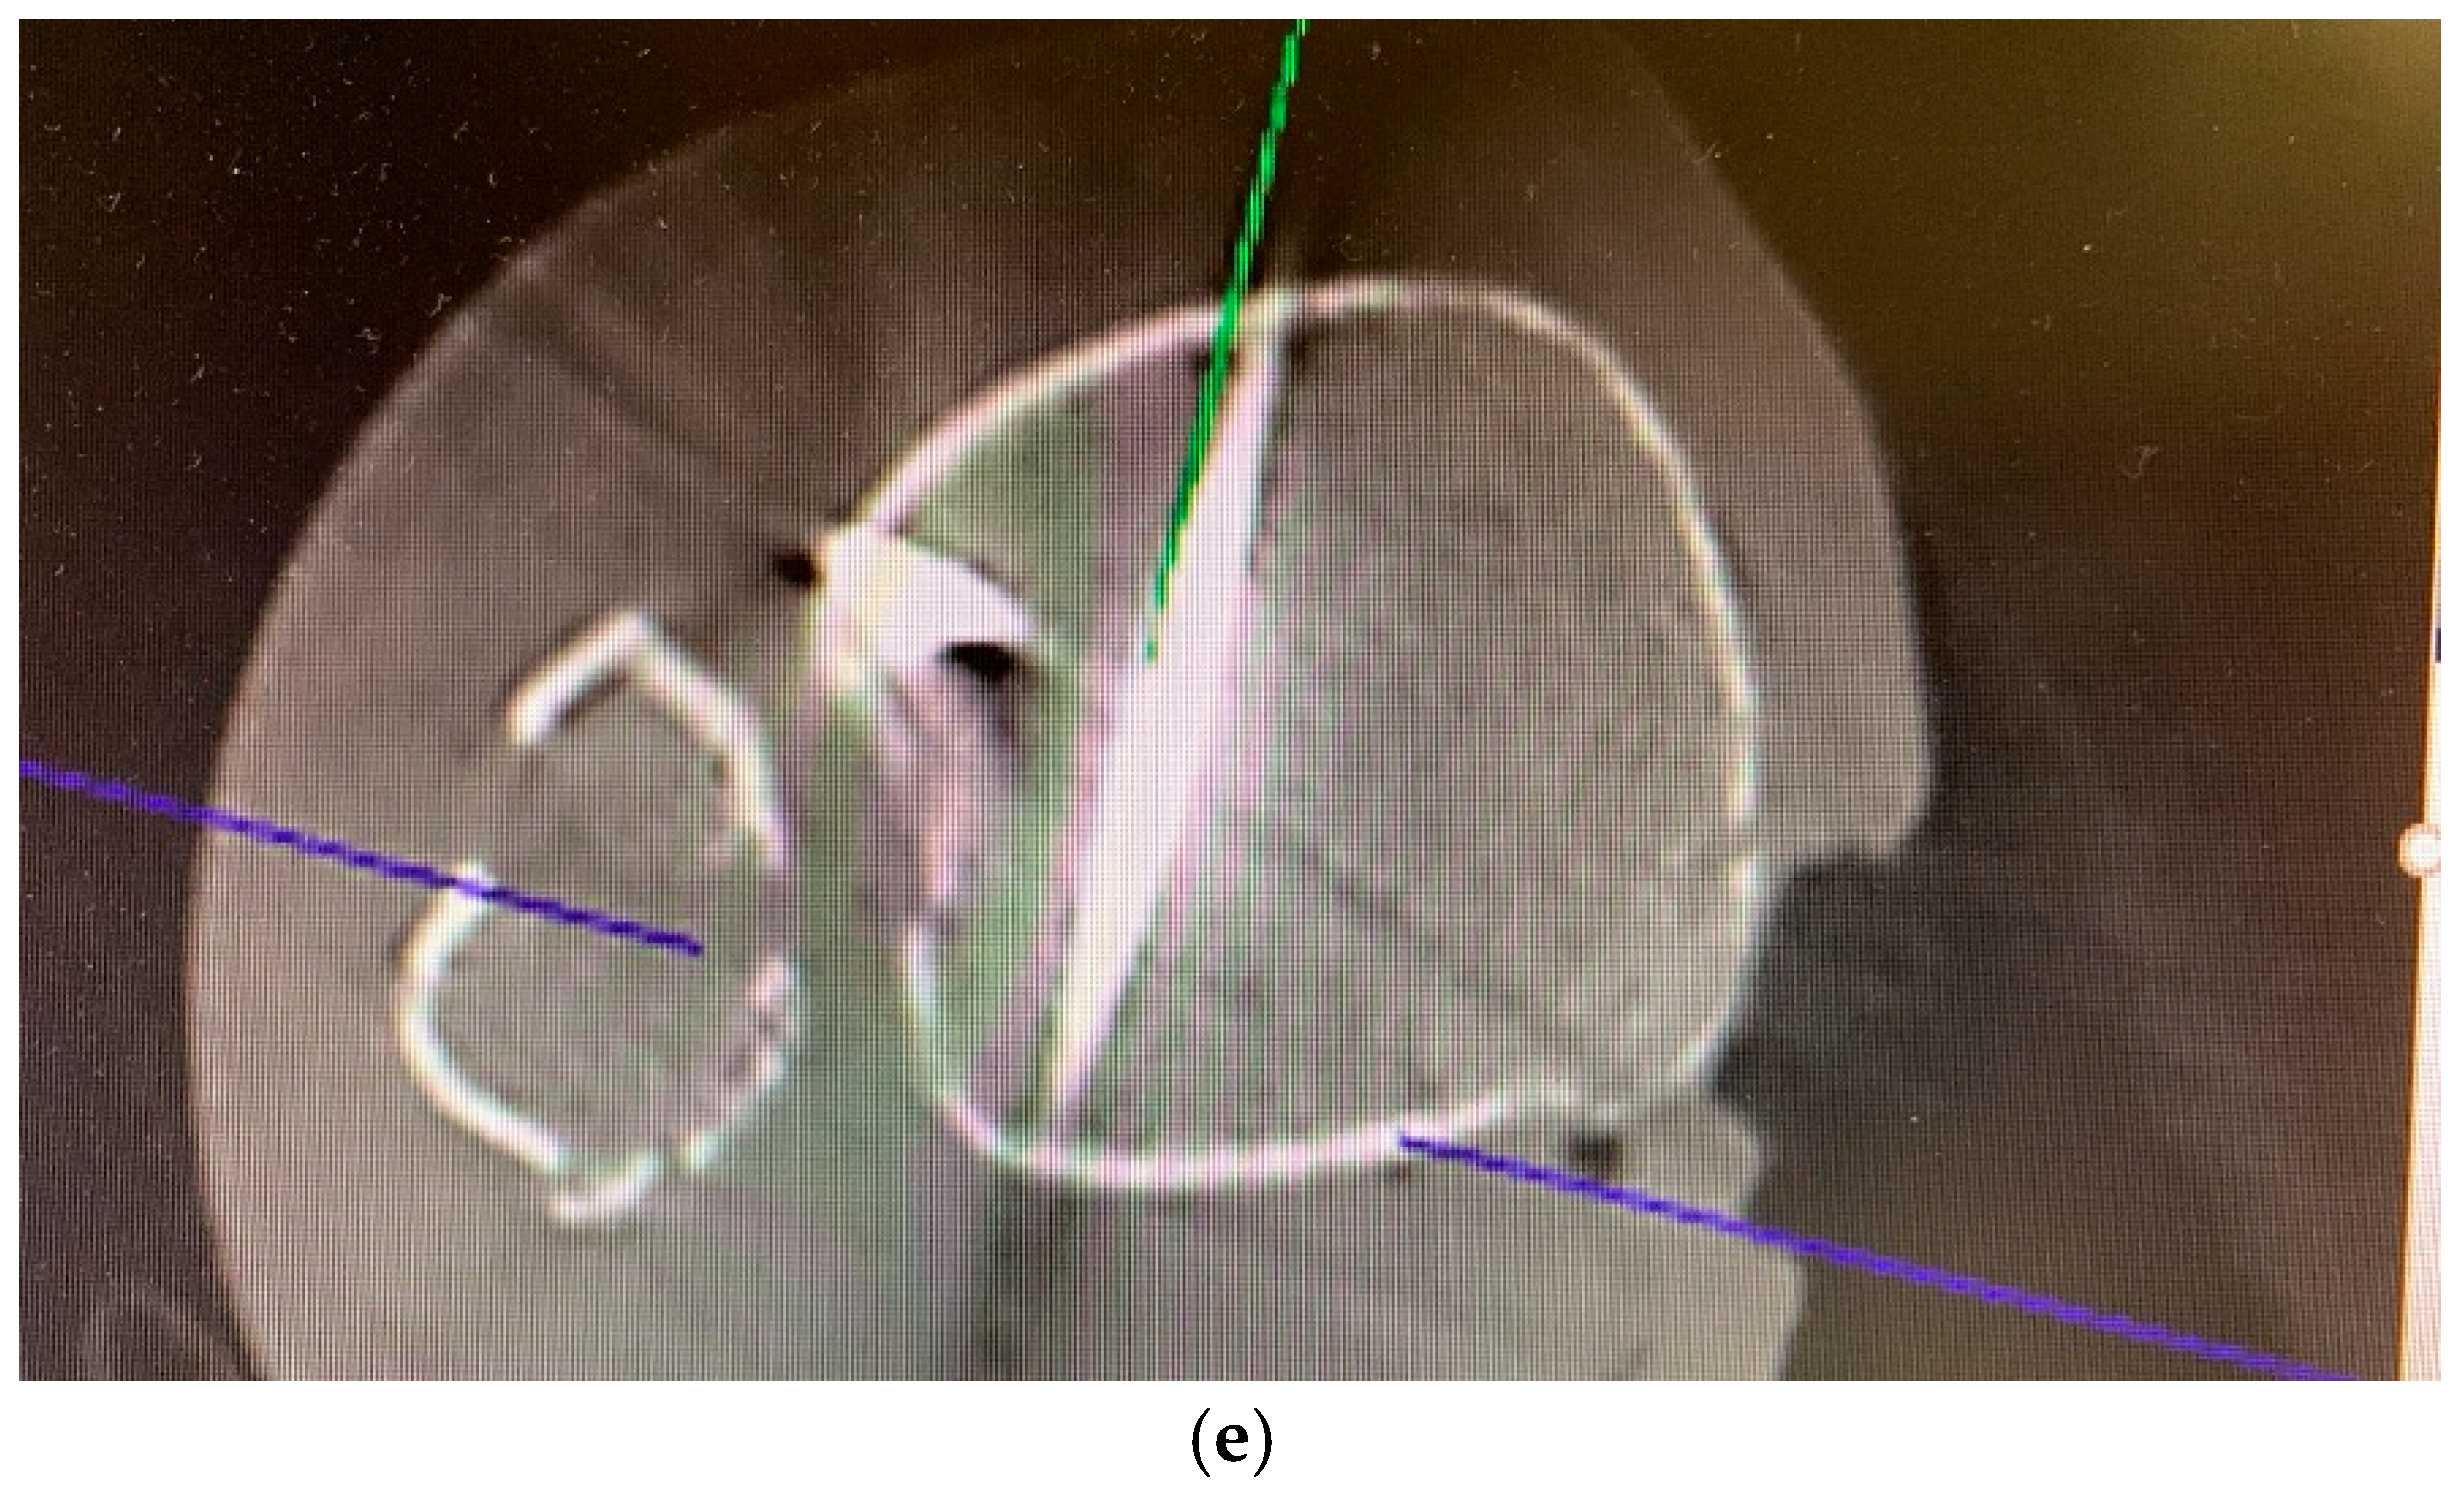

3. Intraoperative 3D Fluoroscopic Control

5.2. Inside-Out Fixation of the Posterior Malleolus Using a Headless Double-Threaded Compression Screw